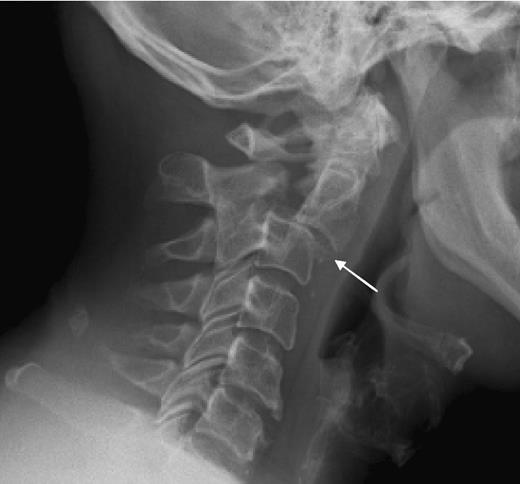

clay shoveler’s fx

avulsion fx of the spinous process C6-T1, results from hyperextension of the neck

teardrop fx

comminuted vertebral body w/ triangular fragments extending from body; caused by compression & hyperflexion of c-spine, best demoed on lateral or CT